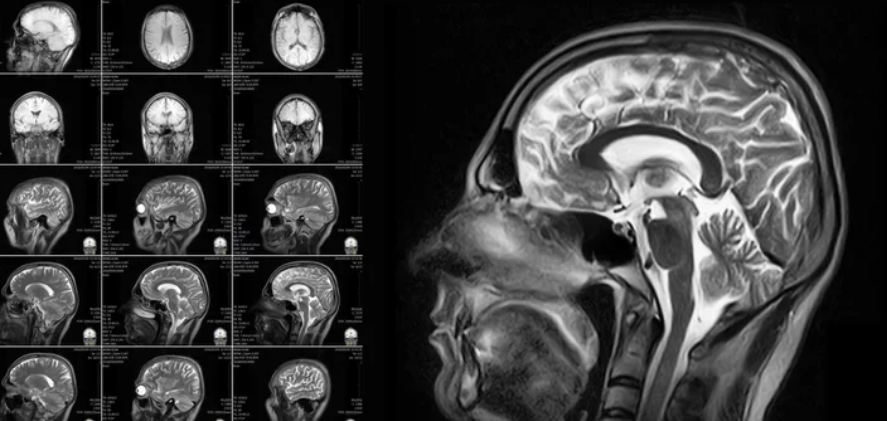

Magnetic Resonance Imaging (MRI) is widely used for diagnostic purposes, renowned for its safety profile due to the absence of ionizing radiation. However, concerns have occasionally arisen regarding whether MRI could potentially increase cancer risk. This review critically examines the scientific evidence to address this question.

• How MRI works: MRI employs strong magnetic fields and radiofrequency (RF) pulses to generate images.

• No ionizing radiation: Unlike X-rays or CT scans, MRI does not emit ionizing radiation, which is a known carcinogen.